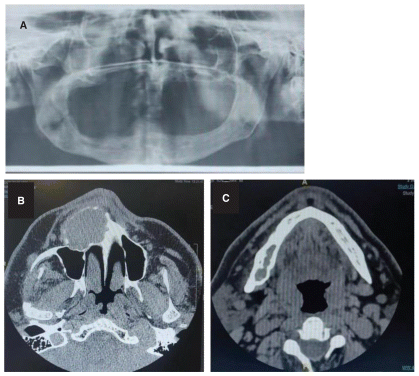

A CT scan (Figure 1) showed an extensive osteolytic lesion in the right maxilla, causing obliteration of the maxillary sinus and erosion of both the buccal and palatal cortical plates. A second, well-defined round osteolytic lesion was also observed at the right mandibular angle. This lesion had radiologic features similar to those of the maxillary lesion.

Radiographically, CGCG appears as a unilocular or multilocular radiolucency, often linked to expansion and thinning of the cortical bone, root resorption, and sometimes, perforation of the cortical plates [10]. In our patient, the lesion resulted in obliteration of the maxillary sinus and erosion of both buccal and palatal cortices. Additionally, a second asymptomatic lesion was identified in the right mandibular angle during imaging, consistent with documented cases of multifocal involvement [11].